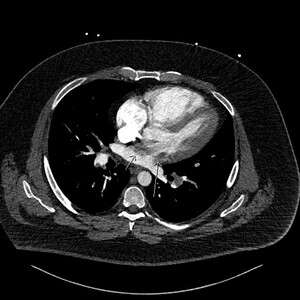

Figure 4 is a coronal image and shows the thrombus in transit again with a “boomerang” shape across the IAS (arrow heads).